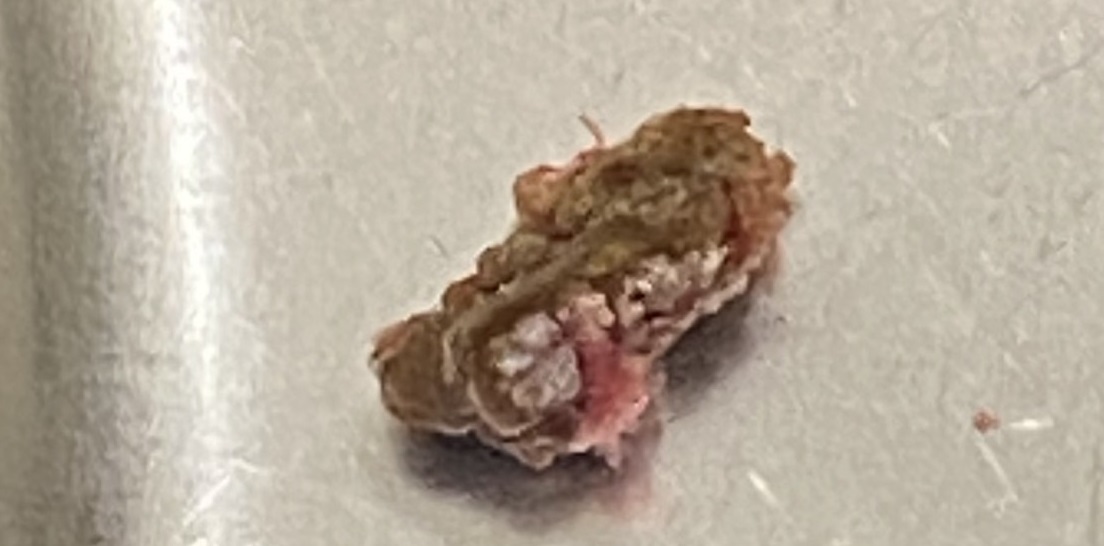

Hình ảnh viên sỏi được lấy ra